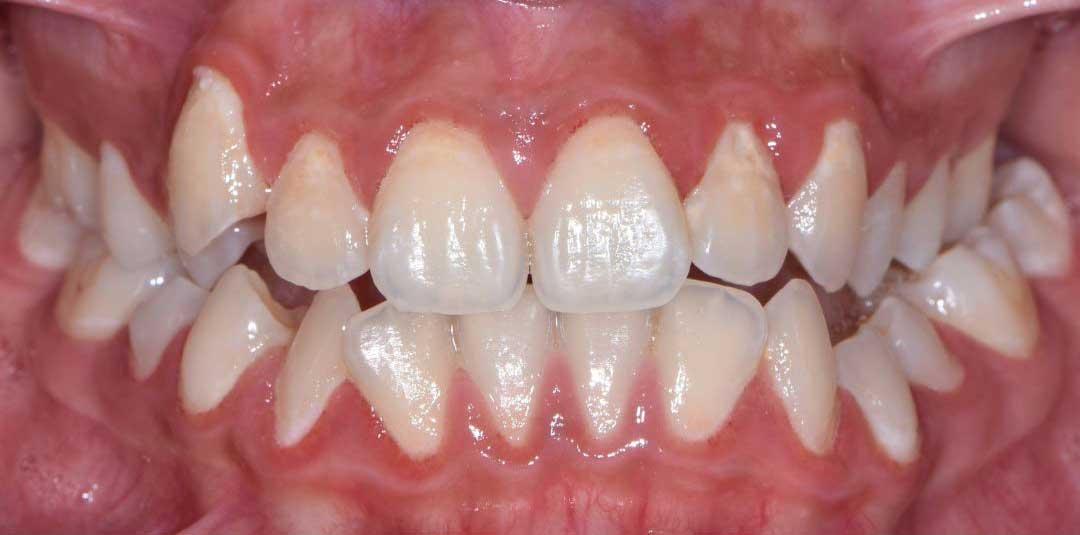

Beautiful Smiles

by Dr. Paolo Bellini